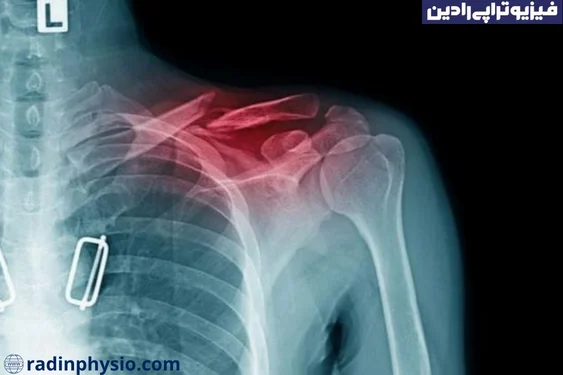

شکستگی ترقوه یا کلاویکل چیست و چگونه ایجاد میشود؟ فیزیوتراپی شکستگی ترقوه یا کلاویکل چگونه انجام میشود؟ شکستگی ترقوه یا کلاویکل به معنی شکستگی استخوانی که در ناحیهی ترقوه (کلاویکل) اتفاق میافتد، است. ترقوه یا کلاویکل یک استخوان مهم در قسمت بالایی صدر قفسه سینه است که به استخوان ستون فقرات و شانه متصل میشود.

در صورت مشاهدهی علائم شکستگی ترقوه، توصیه میشود به یک پزشک مراجعه کنید. پزشک با استفاده از امکانات تشخیصی مانند اشعه ایکس و معاینه فیزیکی، میزان شکستگی را تشخیص داده و درمان مناسب را تعیین خواهد کرد.

- تصویربرداری: تصویربرداری مانند ایکسری از استخوان ترقوه ممکن است برای تشخیص شکستگی استخوان استفاده شود. این تصاویر میتوانند نشان دهنده شکستگی، جابجایی قطعات شکسته یا تغییرات در استحکام استخوان باشند.